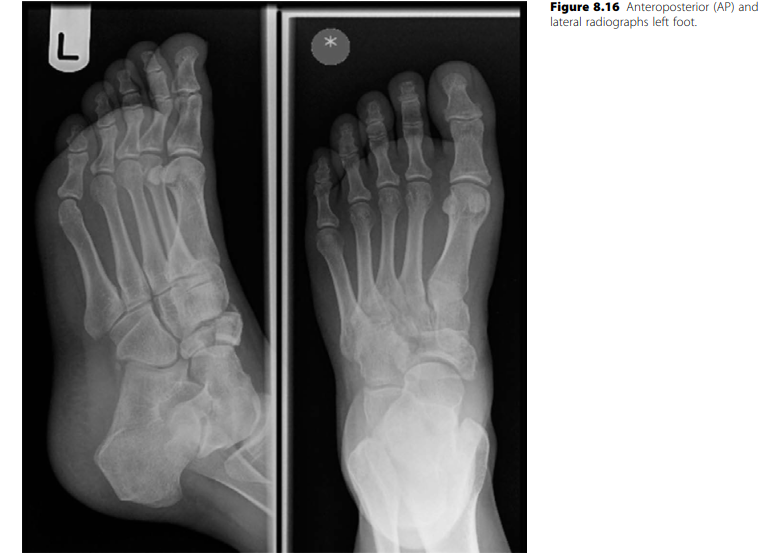

Lower limb Trauma Structured oral examination question 9 A 29-year-old female horse rider fell off her horse;…